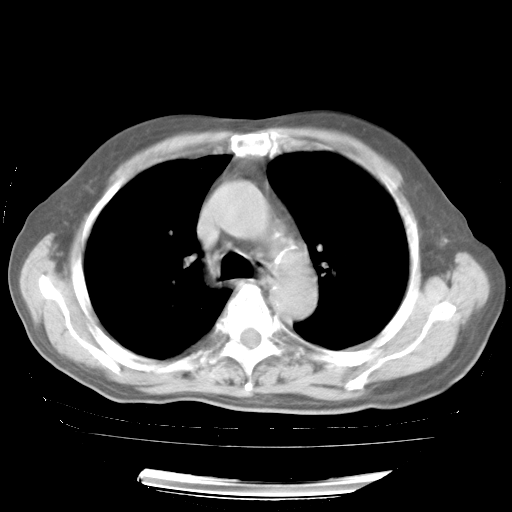

4月28日肺部CT——再次出现类似去年5月9日——透光度降低,“间质性”改变。

4月28日肺部CT——再次出现类似去年5月9日——磨玻璃样、间有“粟粒样”改变。